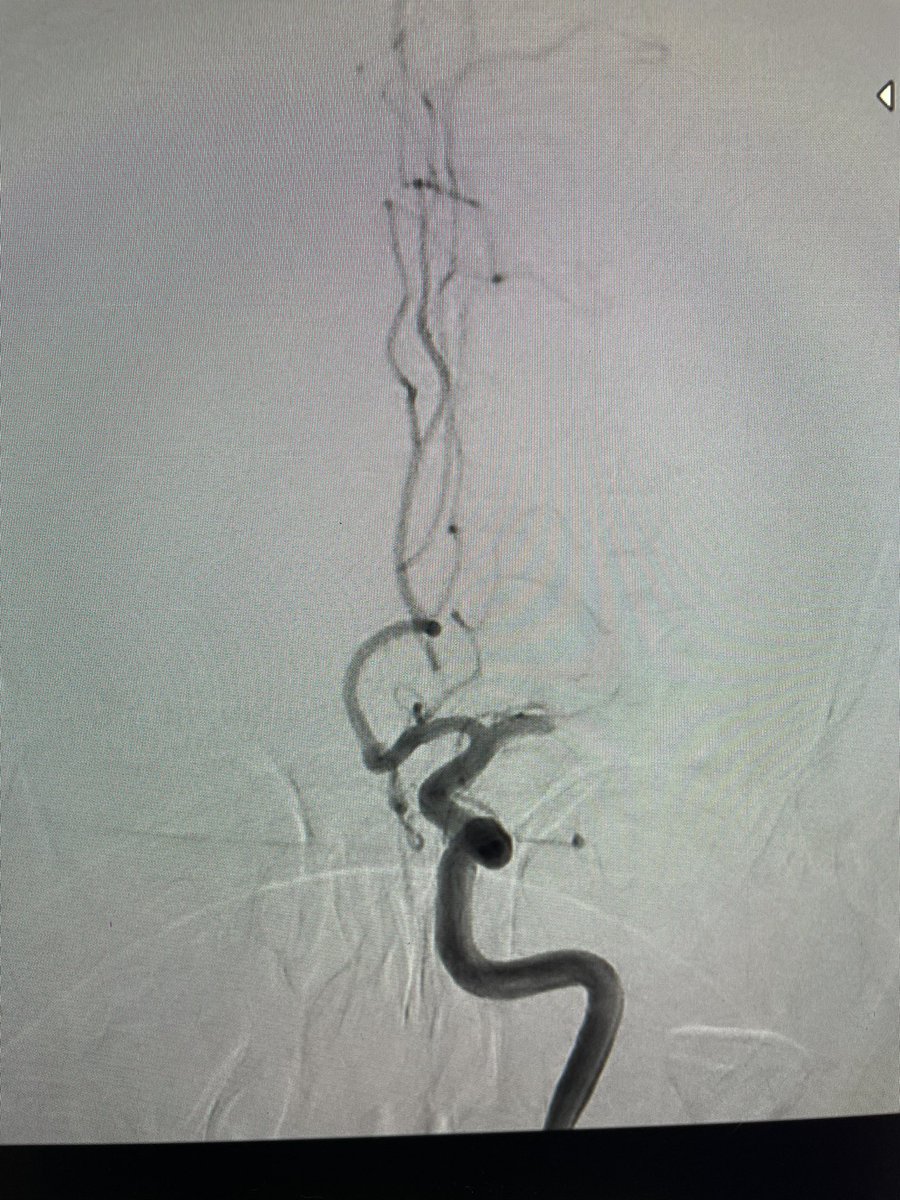

El Dr. Carlos Pérez@Justcharly9, nos resume en menos de 15 minutos los dos principales ensayos clínicos que comparan tratamiento Endovascular VS Quirúrgico (ISAT, IBRAT) de aneurismas rotos.